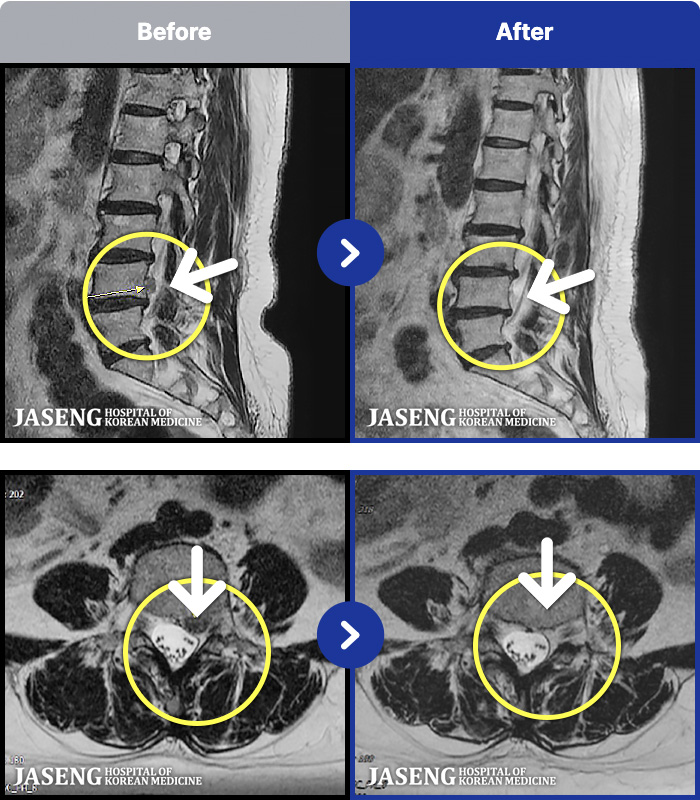

- MRI ġ

MRI ġ

1,301 MRI ũ ʸ Ȯϼ.